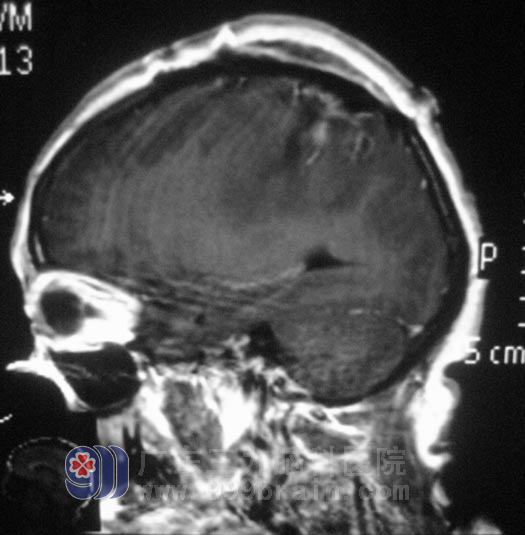

在广东三九脑科医院进一步检查,头颅MR检查提示右侧额顶部占位性病变,大小约4.3cm×4.2cm×2.2cm,考虑脑膜瘤。综合神经外科 鲁明主任为王女士在全麻下行右侧额顶部脑膜瘤切除术,术中切开硬脑膜后,显微镜下见肿瘤与硬膜粘连紧密,位于额顶部,肿瘤部分呈灰白色,质地、血运一般,与脑组织边界较清,予肿瘤全切。术后王女士没有出现肢体偏瘫等不良并发症。术后经病理证实为:合体型脑膜瘤。

▲手术后